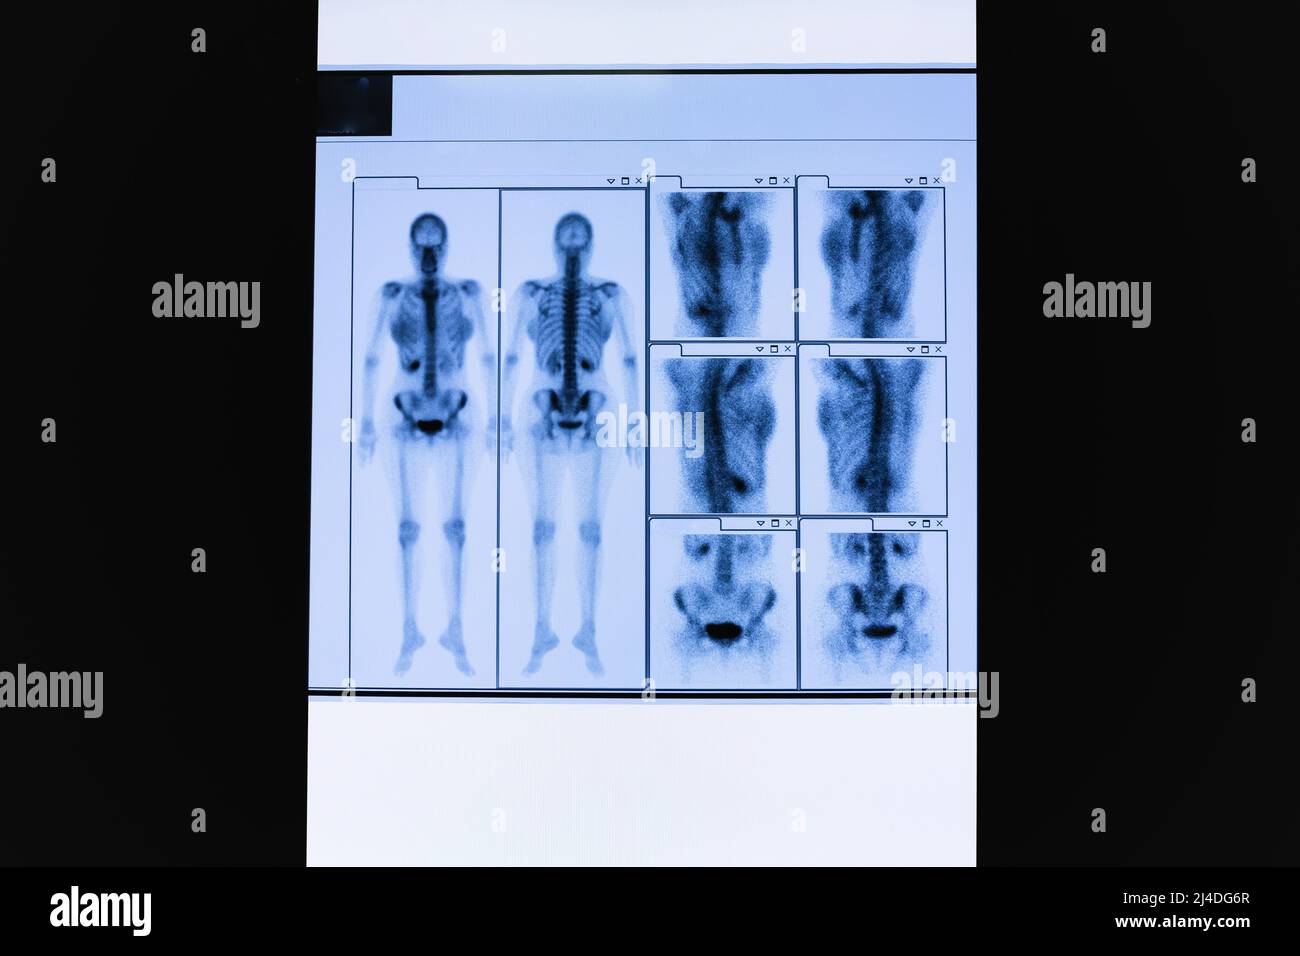

Ensemble d'acquisition CT du squelette du corps entier femelle et des organes internes. Banque D'Imageshttps://www.alamyimages.fr/image-license-details/?v=1https://www.alamyimages.fr/ensemble-d-acquisition-ct-du-squelette-du-corps-entier-femelle-et-des-organes-internes-image467436671.html

Ensemble d'acquisition CT du squelette du corps entier femelle et des organes internes. Banque D'Imageshttps://www.alamyimages.fr/image-license-details/?v=1https://www.alamyimages.fr/ensemble-d-acquisition-ct-du-squelette-du-corps-entier-femelle-et-des-organes-internes-image467436671.htmlRF2J4DG6R–Ensemble d'acquisition CT du squelette du corps entier femelle et des organes internes.